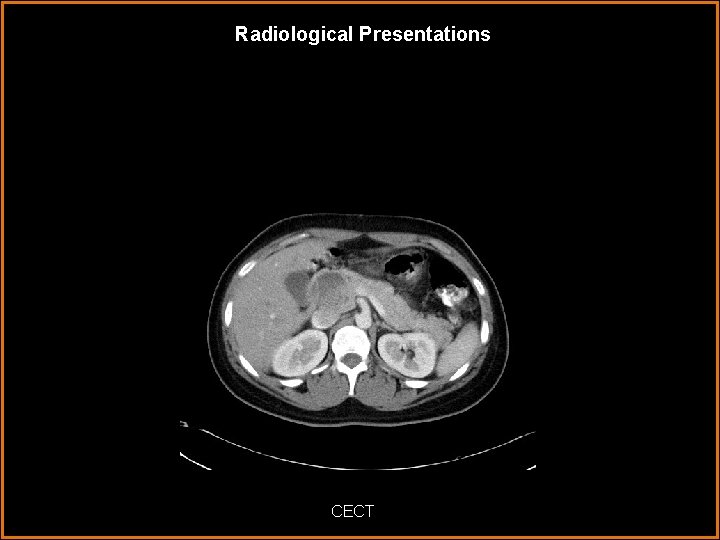

Radiological Presentations CECT

Findings and Differentials Findings: CT: There is a large pacreatic head mass with heterogeneous attenuation. Solid and cystic portions are noted surrounded by a sharply demarcated enhancing capsule. No calcifications, internal septations or central scar is identified. MRI: Mass shows high and low intensity signal on T 1 and T 2 weighted images with predominantly hyperintense features on T 2. It is well circumscribed with a distinct T 2 hypointense fibrous capsule. Pre-contrast T 1 images show areas of high signal corresponding with low signal on T 2 representing hemorrhage. There is early intense enhancement of the capsule and mild heterogeneous central enhancement of the solid portions. The internal enhancement is less intense than the normal pancreatic parenchyma. No pancreatic duct dilatation is present. Differentials: • Solid Pseudopapillary Tumor of the Pancreas

Discussion Characteristic Imaging Features of SPT CT: Typical features of SPT on CT are a large well-defined encapsulated mass with solid and cystic components caused by hemorrhage. Calcification are often seen along the periphery. Enhancement of the capsule and solid structures within the mass are also characteristic. MRI: The appearance on MRI classically shows a well-defined mass with a low signal capsule on T 2 weighted images. The tumor will have a mix of high and low signal intensity on T 1 and T 2 weighted images. The areas of high signal on T 1 and low or inhomogeneous signal on T 2 help identify hemorrhage which is the key finding in SPT that helps differentiate it from most other pancreatic tumors. The enhancement pattern shows early peripheral enhancement of the capsule and solid portions with progressive fill-in of the tumor.